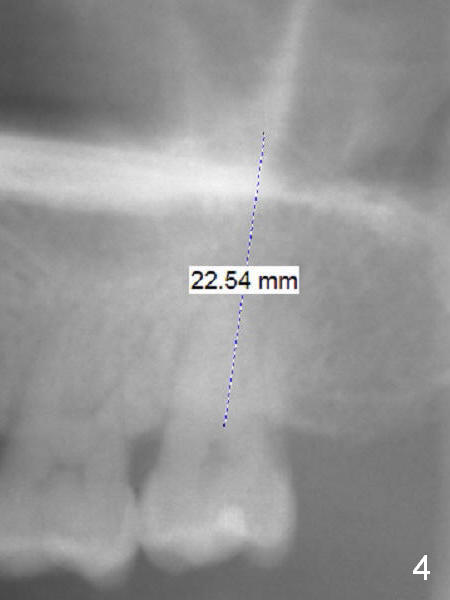

A 54-year-old lady has history of chronic periodontitis, characterized by bone loss (Fig.1 <, 2) . Her oral hygiene is fair. Bone loss and obliterated canals at #14 (Fig.1) are apparently related to bruxism. The latter seems to cause crack tooth at #15 with infection lately (Fig.3). Since the bone height is plenty (Fig.4), the longest implant will be used (5-7x20 mm (tissue-level) or 5.5x13 mm or longer (bone-level, Fig.5)). Use 2 mm drill to measure the socket (Metronidazole) depth and osteotomy will be at least 6 mm in the new bone. In fact, the tooth #14 is found to be affected when the patient returns from a periodontist's office (Fig.3).